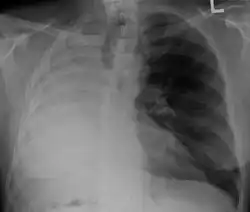

Anatomical changes

After a pneumonectomy is performed, changes in the thoracic cavity occur to compensate for the altered anatomy. The remaining lung hyperinflates as well as shifting over along with the heart towards the now empty space. This space is full of air initially after surgery, but then it is absorbed, and fluid eventually takes its place.[9] The fluid which fills the residual space in the chest cavity slowly gelatinizes into a proteinaceous material, and the chest scaffold collapses slightly.